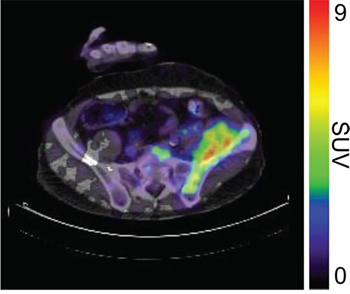

In 6 out of 10 patients, target lesions were visually assessed positive for 89Zr-cetuximab uptake. Figure 4A and 4B shows examples of visible 89Zr uptake in a metastatic lesion of the iliac bone (patient 8) and the lung (patient 10). In Figure 4C, another lung lesion in patient 10 shows no uptake. Most tumor lesions showed increasing uptake in time, indicating accumulation of cetuximab. SUVpeak of these lesions varied between 2.2–7.5 on day 6 p.i.. Figure 4D illustrates the photopenic aspect of liver metastases within normal liver tissue accumulating high amounts of 89Zr-cetuximab. Two of the 3 patients who were scanned at day 10 p.i. had visible 89Zr-cetuximab uptake. SUVpeak at day 10 increased compared to day 6 in patient 8 (from 7.3 to 10.3), but was comparable in patient 6 (3.17 and 3.36, Figure 4E Due to the physical half-life of 89Zr, image quality deteriorated over time, making day 6 p.i. the optimal scanning time point. Visually negative tumor sites had SUVmean of 1.0–1.9 at day 6 p.i. (Figure 5).

Figure 4D: 89Zr-cetuximab PET scan of patient 3 at day 6 p.i. illustrating high accumulation in healthy liver with relative photopenic area's in metastases.